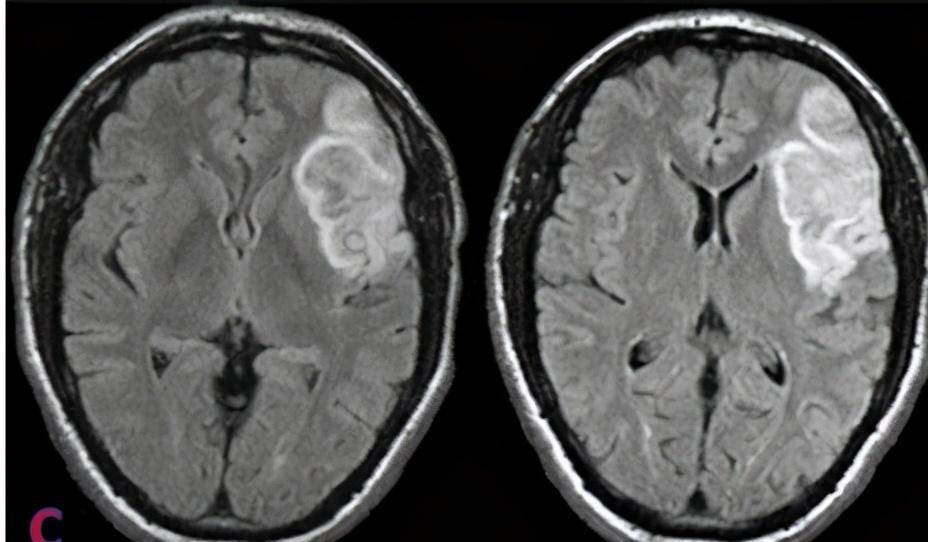

动脉斑块脱落风险大,该如何预防?医生:这2类人尤其要注意!动脉斑块,医学上称为动脉粥样硬化,是动脉壁上沉积的脂肪、钙质和纤维组织形成的斑块。这些斑块随着时间的推移会逐渐增大,导致动脉管腔狭窄,影响血液流动。更为严重的是,当斑块不稳定时,可能会发生破裂或脱落,形成血栓,随血流到达较小血管时造成堵塞,引发如心肌梗塞、脑梗塞...